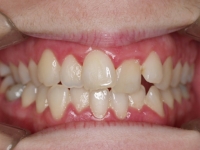

Premolar mandibular incluido + fenestración

45 incluido